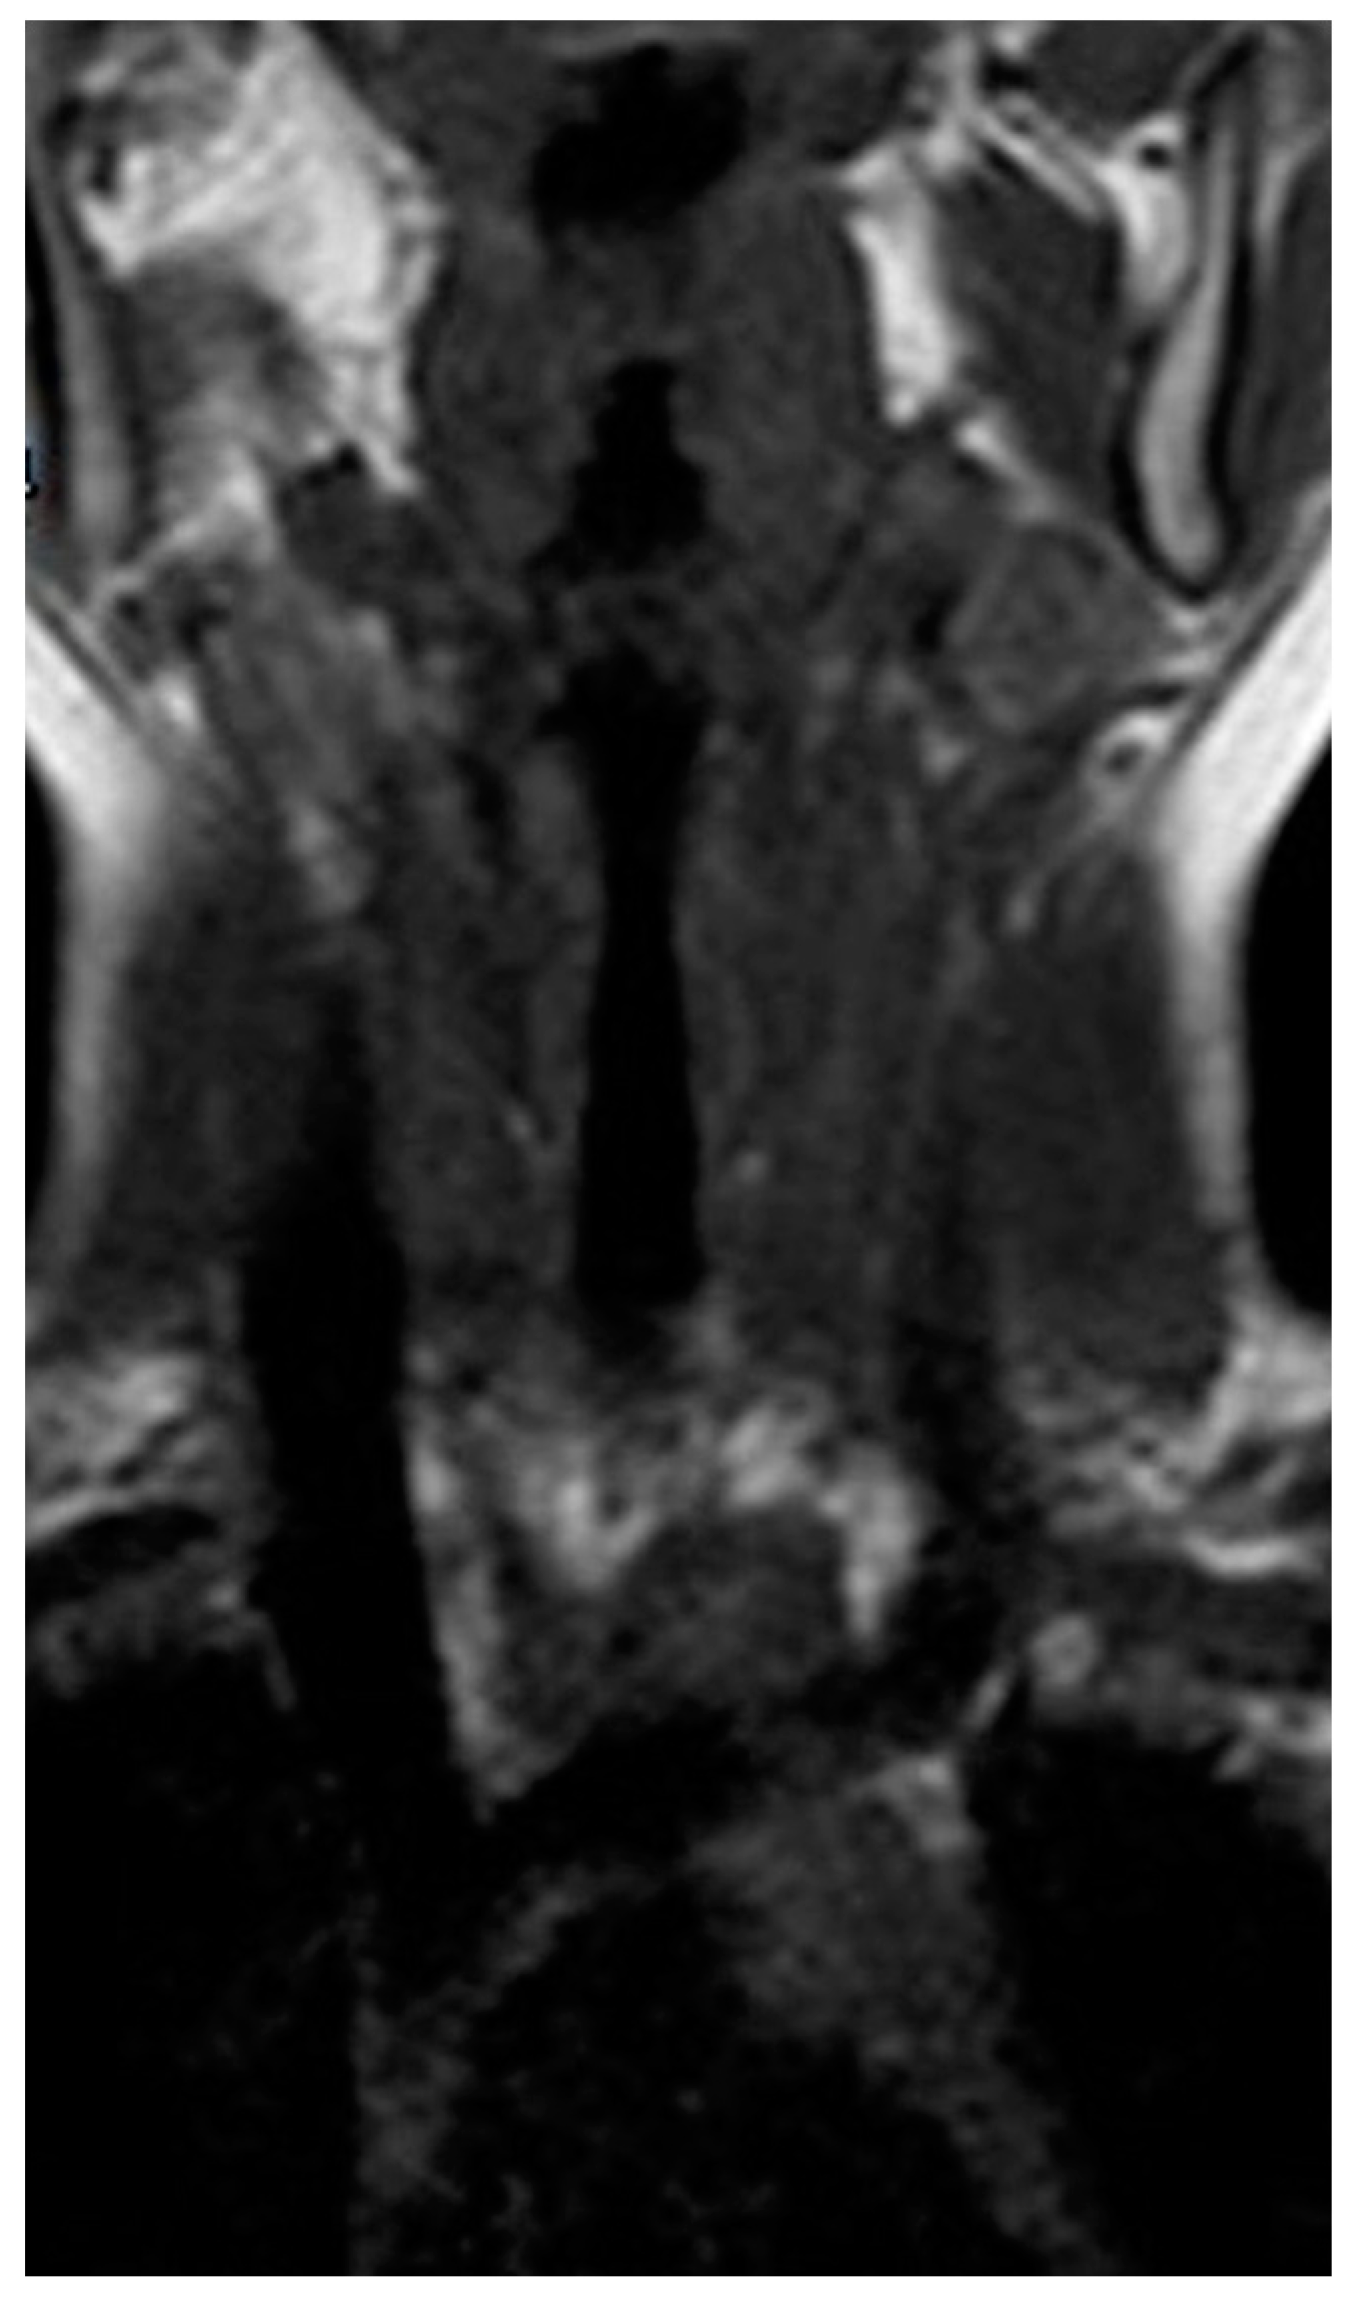

2.2. Investigations for Recurrent Neck Abscesses